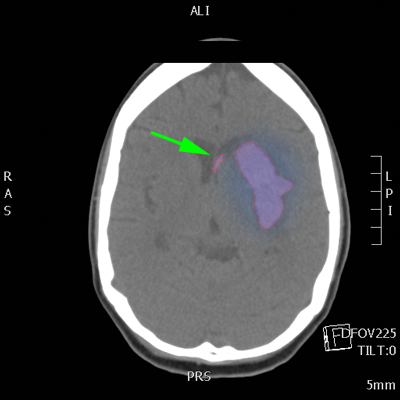

Αυτόματο ενδοεγκεφαλικό αιμάτωμα (κόκκινο περίγραμμα) με περιεστικό οίδημα (μπλέ). Αιμορραγία και στην αριστερή πλάγια κοιλία του εγκεφάλου (πράσινο βέλος). |